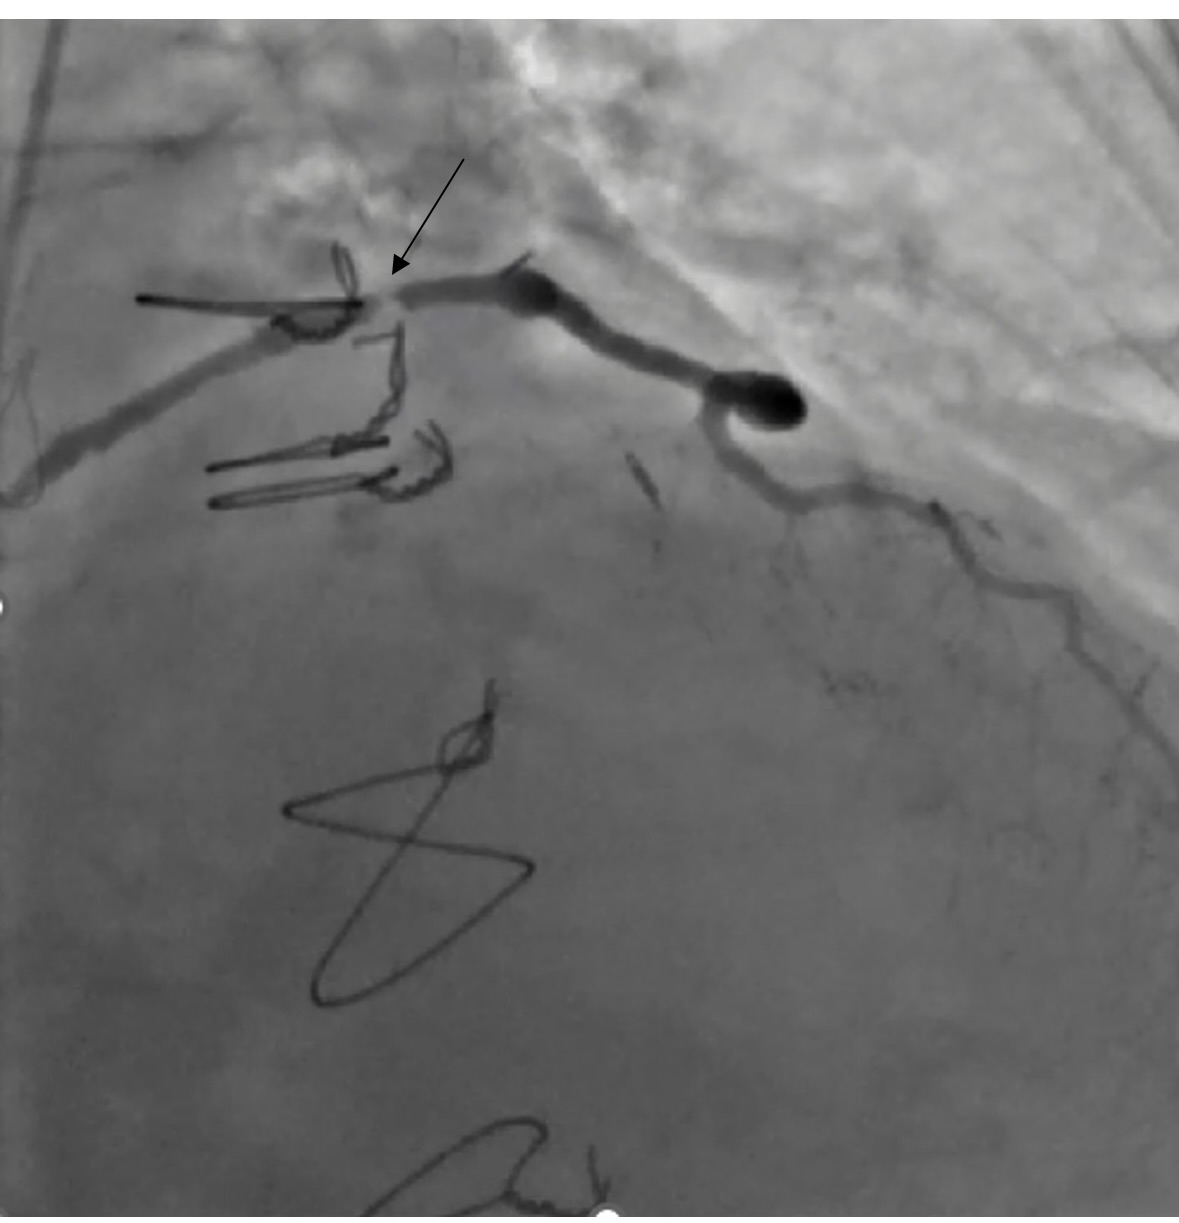

After shared decision-making, high-risk PCI was pursued. We used 7F equipment and an AL 0.75 guide. Angiography confirmed a severely calcified mid and ostial SVG lesion. A workhorse wire crossed the lesion, but neither microcatheter nor balloon could be advanced. These lesion characteristics even made Embolic protection devices (EPDs) infeasible and hence were not used. Laser Atherectomy was avoided due to heavy calcification, and Intravascular lithotripsy (IVL) was not feasible due to its large profile. Rotational atherectomy was pursued as a last resort. A microcatheter was deeply positioned, and a Rota floppy wire was advanced using a primary wiring technique. We then performed rotational atherectomy in the SVG graft with a 1.25 mm burr at 150,000 rpm. No perforation or vessel damage was seen. Subsequently sequential balloon angioplasty and stenting with 2.75 x 38 and 2.75 x26 mm stents were placed from distal graft body to ostium with significantly improved blood flow in the graft. Bailout strategies, including vascular plugs, coils, covered stents, and vasodilators, were prepared, alongside plans for prolonged DAPT.

Discussion: SVG calcification involves the vessel wall, leading to diffuse disease and higher PCI risks due to small distal vessels, recoil, and disease beyond the graft. Atherectomy is usually avoided in SVGs due to limited data and risks like embolization, perforation, no-reflow, and MACE. It is recommended to use EPDs to reduce the risk of distal embolization, no-reflow, and periprocedural MI. Vasodilators, direct stenting, and undersized stents may help mitigate no-reflow and distal embolization. In this case, technical limitations, extreme calcification and failure to cross the lesion with standard devices necessitated rotational atherectomy. This case supports the selective use of rotational atherectomy in complex SVG lesions and emphasizes the need for further study to guide management.